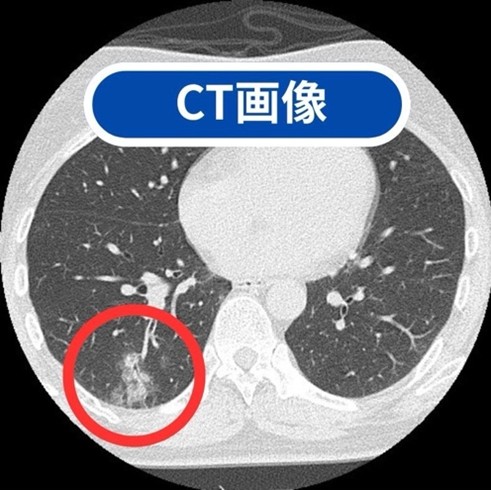

実際に、AIが「ここが怪しいですよ」と教えてくれた部分をCTで詳しく調べたら、肺炎が見つかったこともありました!

- 胸部CT検査

- 肺がん・肺炎・結核・肺気腫・気胸・慢性気管支炎など主に肺の病気の診断に有効